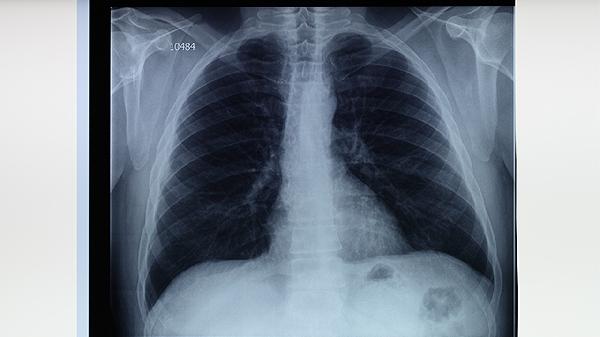

肺结核患者除规范用药外,需保证高蛋白、高维生素饮食以支持免疫修复,适当补充乳制品、鸡蛋及新鲜蔬菜水果。治疗期间须严格隔离痰菌阳性者,佩戴口罩并定期消毒居所。完成全程治疗是关键,擅自停药可能导致耐药结核病,建议每月复查胸片和痰涂片直至医生确认治愈。